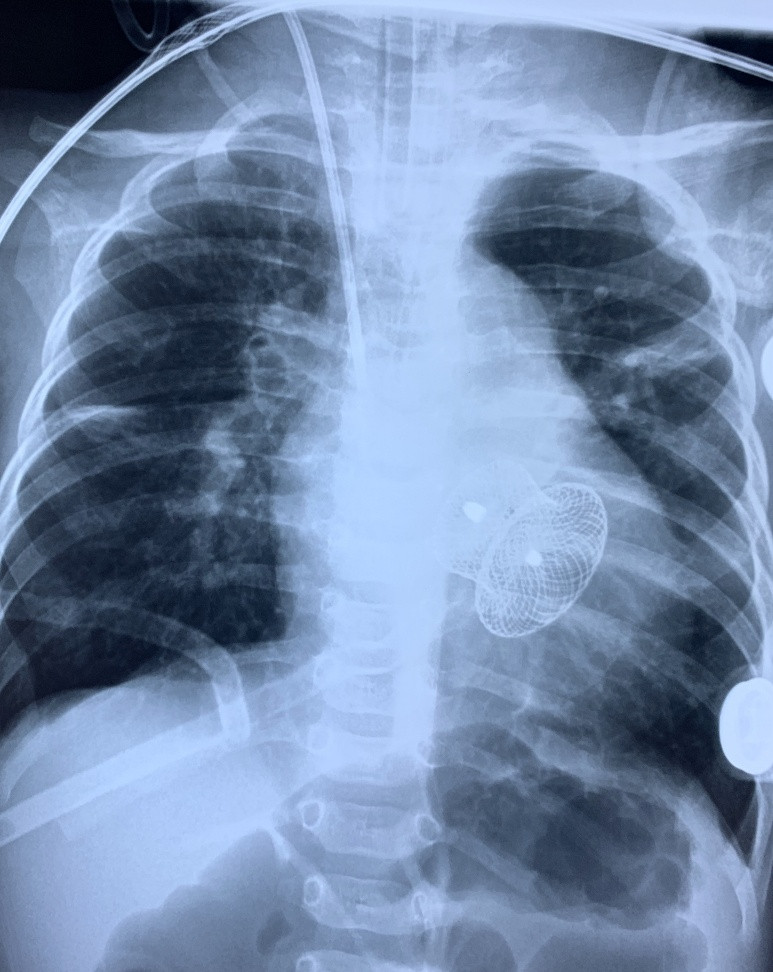

| Phim chụp ngực bệnh nhi sau can thiệp (có hình dụng cụ ở giữa tim). Ảnh: BVCC |

Sau khi hội chẩn, Trung tâm Tim mạch và Lồng ngực quyết định dùng kỹ thuật Hybrid để điều trị cho bệnh nhi, mặc dù rất khó khăn nhưng là giải pháp trọn vẹn nhất. Kỹ thuật Hybrid trong tim mạch là sự kết hợp cùng lúc 2 kỹ thuật cao là “phẫu thuật tim mạch” và “can thiệp tim mạch” để điều trị các bệnh phức tạp mà 1 trong 2 kỹ thuật cao này không thể giải quyết tốt được.